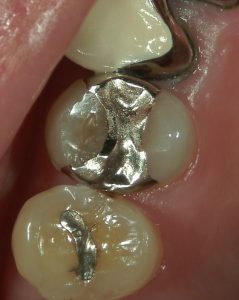

治療前後の写真です。

当院ではこのように精密審美治療に、神経を保護するための歯髄保存治療をオプションとして受けていただける環境を提供しています。

優れた材料に頼るのではなく、それらや歯の状態をより活かすことができるよう努めています。

歯髄保存治療は歯を抜かない、削らないというコンセプトに、より根拠を持たせる治療法です。